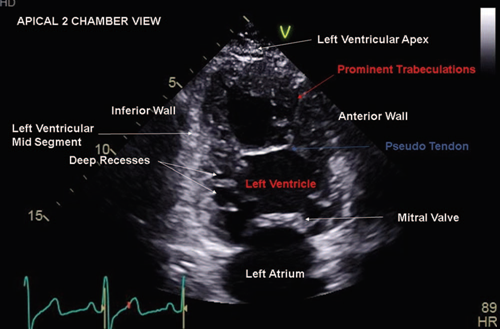

Isolated left ventricular noncompaction cardiomyopathy (ILVNC) is a rare genetically heterogeneous condition characterized by hypertrabeculation and sponge-like appearance of the left ventricular myocardium (Fig. 1). ILVNC can be congenital in nature or acquired later in adult life. In addition, sporadic occurrence and familial transmission have been described.1-3

Figure 1 Apical 2 chamber view displaying hypertrabeculation in left ventricular non compaction cardiomyopathy.